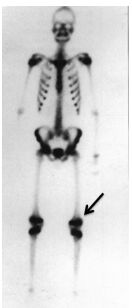

31.下圖為一位15歲小孩注射 99mTc-MDP 3小時後的骨骼造影,圖中箭頭所指活性增高的原因為何?(A)骨質疏鬆(osteoporosis) (B)運動傷害(sport injury) (C)骨腫瘤(bone tumor) (D)生長板(growth plate)